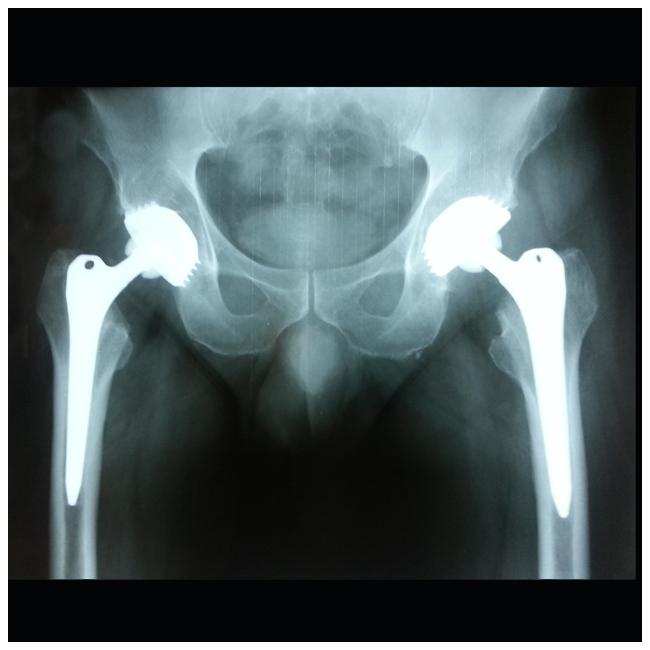

Αρθοπλαστικές Χαλάνδρι, Επανορθωτική χειρουργική Χαλάνδρι